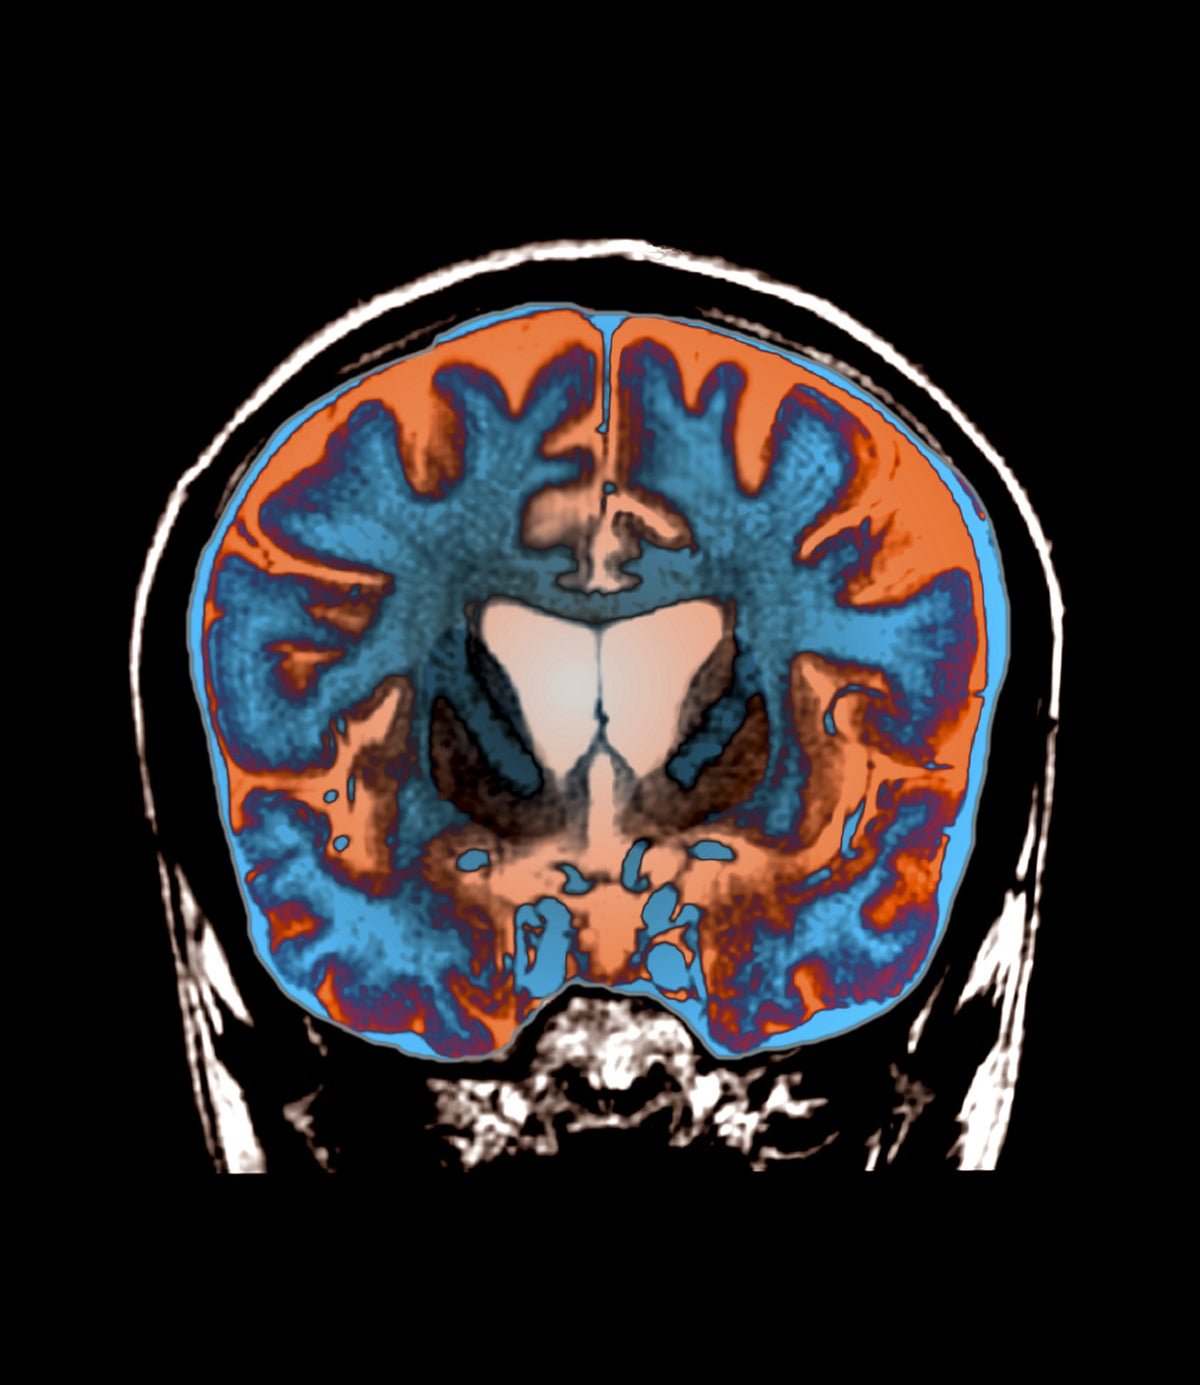

In some ways, Huntington’s disease seems like it should be the easiest neurodegenerative condition to treat. Unlike Parkinson’s and Alzheimer’s, scientists know exactly what causes Huntington’s: a mutation of the HTT gene in which a short, three-letter DNA sequence is repeated many times, causing it to produce a faulty version of the huntingtin protein. These faulty proteins accumulate in a deep brain structure called the striatum and cause symptoms such as uncontrollable movements, muscle spasms and cognitive decline that worsen over time.

Unlike ASOs, the new gene therapy drug AMT-130 is a one-time treatment, but it also involves lengthy and invasive brain surgery. Physicians insert catheters into deep parts of the brain where they can deliver the AMT-130 drug right to the neurons in the striatum that produce the abnormal huntingtin protein. The medication is transported through “shuttles” called adeno-associated viruses—noninfectious viral shells that can be packaged with genetic material. This genetic payload enters neurons, where it continuously produces tiny pieces of genetic code called microRNA. These microRNA specifically target and degrade messenger RNA carrying the instructions to build more huntingtin protein, therefore lowering the amount of huntingtin protein in the cell.